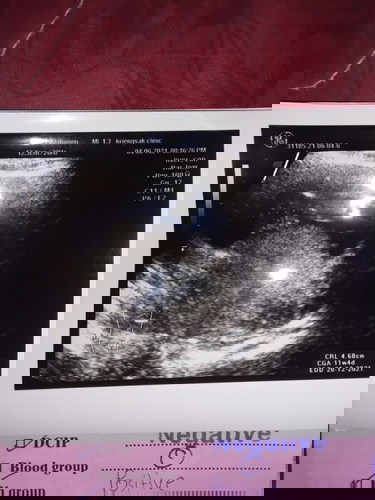

อยากรู้จังค่ะ

ว่าเป็นลูกสาวลูกชาย

ดูไม่ออกเลยค่ะว่าส่วนไหน

กำลังจะเป็นแม่